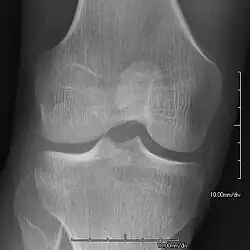

AP radiograph of the right iliac crest showing a bony exostosis or posterior iliac horn, which is pathognomonic of NPS

• Exostoses arising from the posterior aspect of the iliac bones ("iliac horns") are present in as many as 70-75% of patients; this finding is considered pathognomonic for the syndrome.